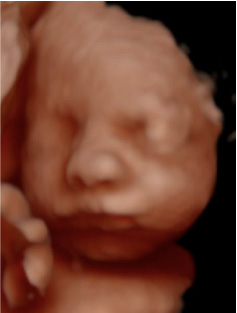

Experimenta la última tecnología hiperrealista 8K, una imagen increíblemente detallada y realista de los rasgos de tu bebé, con una textura y definición que te sorprenderán.

Ecox Alicante ya cuenta con la posibilidad de ofrecer a todos los futuros papis madrileños una experiencia inolvidable gracias a la ecografía 5D y el novedoso hiperrealismo 8K.

Esta nueva tecnología nos permite ofreceros a los futuros papás las imágenes de mayor calidad para que disfrutéis de la experiencia como nunca antes había sido posible.